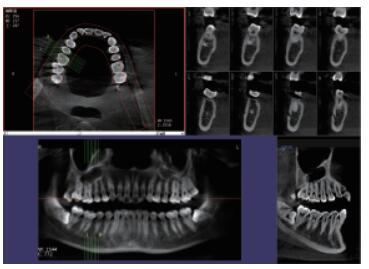

三維重建任意斷層

專(zhuān)有三維重建算法,可提供任意位置高清斷層影像。

高清口腔全景影像

通過(guò)三維容積影像,提取高清口腔全景影像。

多平面組合重建

可同時(shí)觀察軸向面、冠狀面和矢狀面圖像,方便臨床診斷。